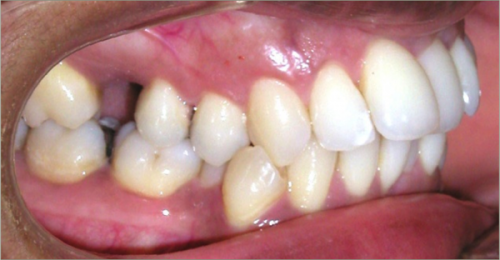

32 year old female:

Diagnosis:

- Previously lost upper first molars

- Severe lower arch crowding

- Midline discrepancy

- Narrow upper arch form

Treatment:

- Extraction of lower right first bicuspid

- Substitution of upper second molars for first molars

- Full fixed appliances

- 23 months